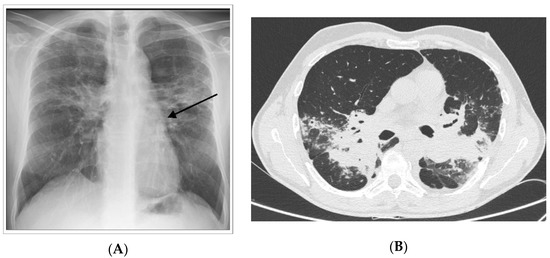

1.1. Lung

- Nunes, H.; Uzunhan, Y.; Gille, T.; Lamberto, C.; Valeyre, M.; Brillet, P.-Y. Imaging of sarcoidosis of the airways and lung parenchyma and correlation with lung function. Eur. Respir. J. 2012, 40, 750–765. [Google Scholar] [CrossRef] [PubMed]